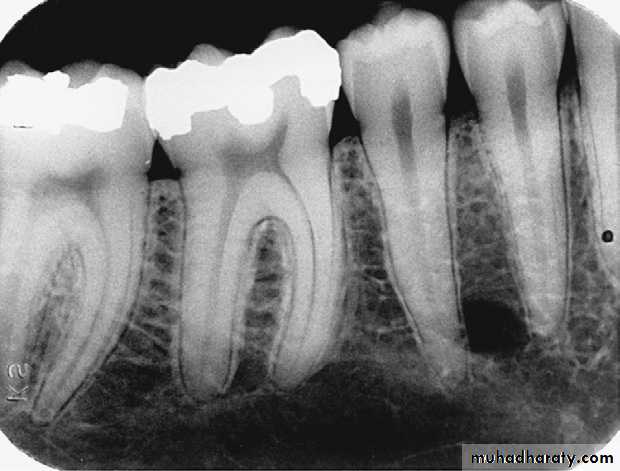

Alveolar crest: The normal healthy alveolar crest is located approximately 1.5 to 2.0 mm apical to the cementoenamel junctions (CEJs) of adjacent teeth.The shape and density of the alveolar crest vary between the anterior and posterior regions of the mouth. In the anterior regions, the alveolar crest appears pointed and sharp and is normally very radiopaque .In the posterior regions, the alveolar crest appears flat, smooth, and parallel to a line adjacent CEJs .The alveolar crest in the posterior regions appears slightly less radiopaque than that in the anterior regions

Healthy alveolar crest in the posterior region that appears flat, smooth, and radiopaque.